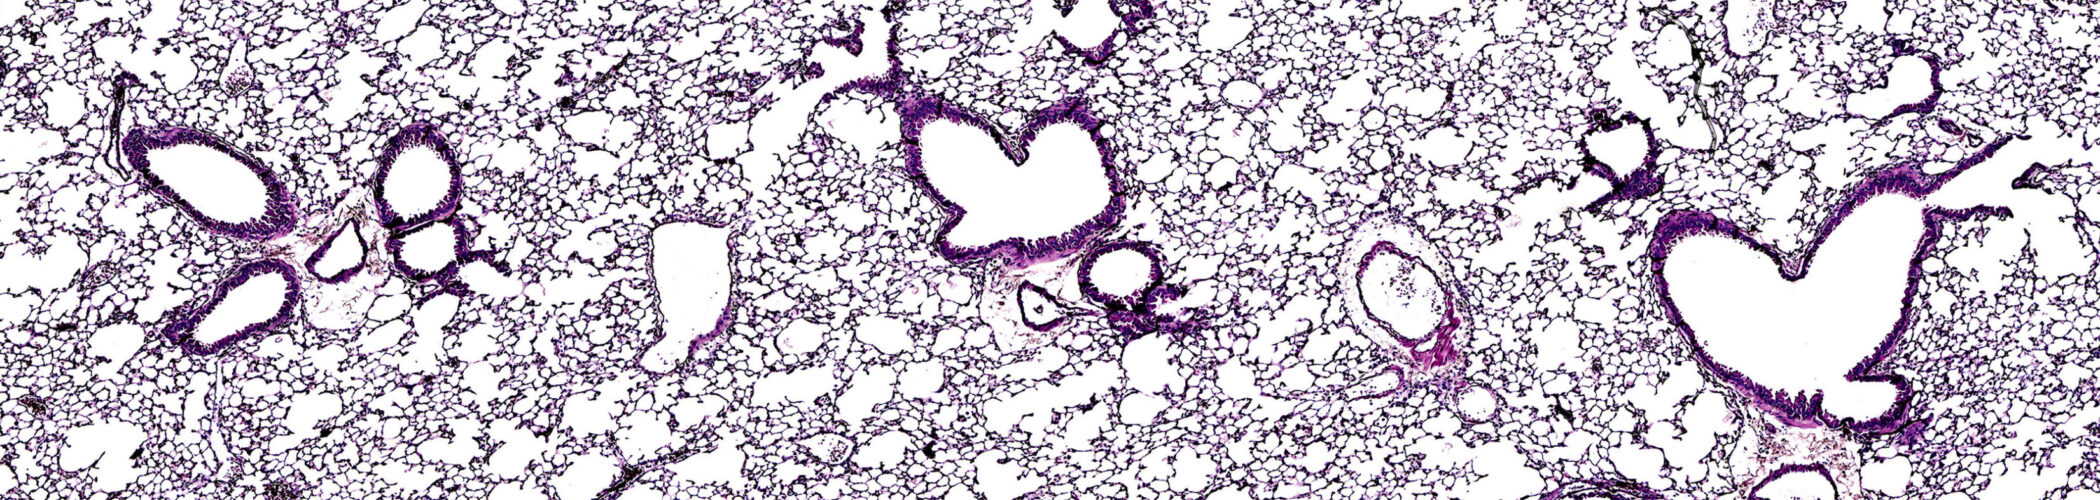

Spatial analysis of target expression in cells, as well as evaluation of differences in the architecture of healthy and diseased tissues, and effects of potential therapeutics, is central to drug development.

We offer a range of techniques, including immunohistochemistry, immunofluorescence and special staining techniques, and have long experience with evaluation of preclinical models including tumor models, neurological models, and inflammation/fibrosis models. We also have access to a large panel of human and rodent tissues, including normal and diseased tissues, to enable customers to gather additional information regarding target localization.

Our comprehensive histology services can provide identification of drug mechanisms and efficacy through evaluation of target engagement and confirmation of mode of action. We support your drug development programs in a wide variety of disease areas